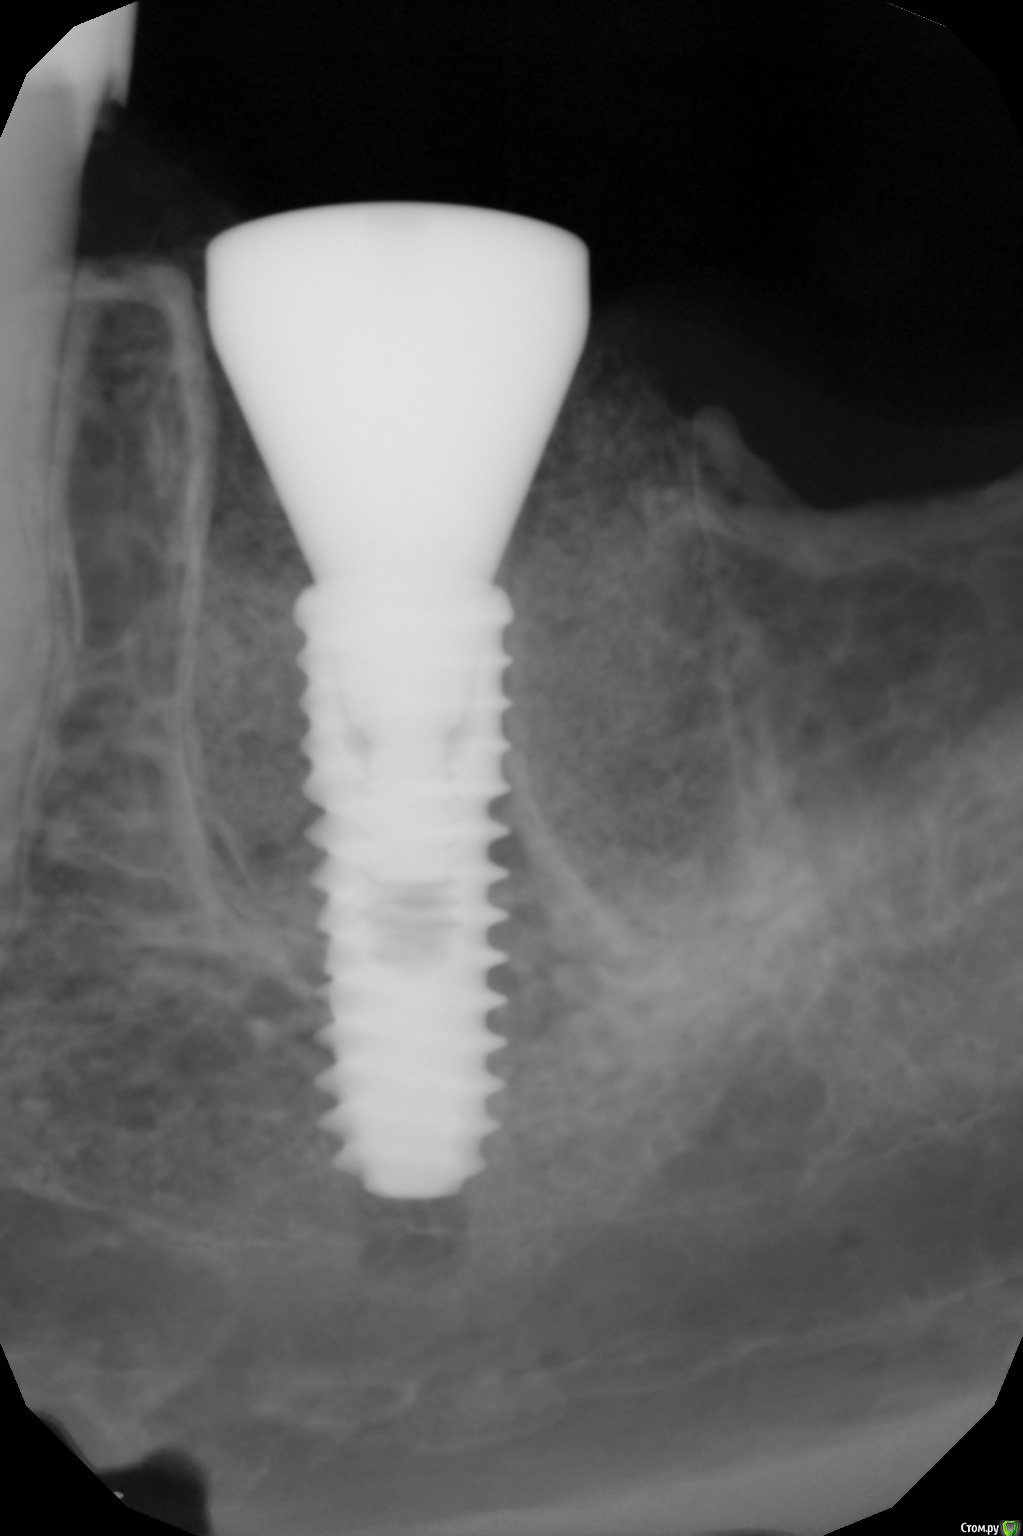

kamranchick Опубликовано 4 февраля, 2017 Поделиться Опубликовано 4 февраля, 2017 (изменено) чтобы не создавать новую тему...Ваши мысли коллеги? между снимками 2 месяца Изменено 4 февраля, 2017 пользователем kamranchick Ссылка на комментарий

Большой Зеленый Опубликовано 4 февраля, 2017 Поделиться Опубликовано 4 февраля, 2017 чтобы не создавать новую тему...Ваши мысли коллеги? между снимками 2 месяцаОткрутить формик и под заглушку.Давление формирователя на кость спровоцировало периимплантит Ссылка на комментарий